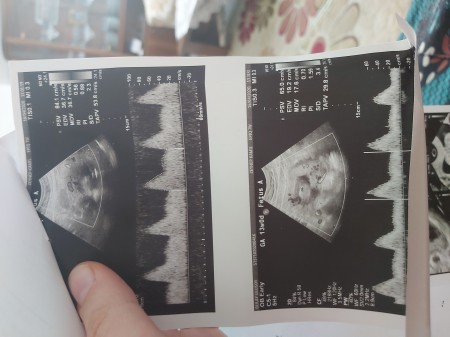

Kızlar ikizlere hamileyim kalo atışı Var mi acaba bu kâğıtta doktora soramadim

Gebelik haftası 13

Fhr yazan yeri bul cok küçük okuyamıyorum ben Fhr de kaç yazıyor atışı benim bu haftalarda 156 falan atıyordu dakikada çok iyi demişti doktor

O çizgilerin olduğu yerde rakamlar var sadece öle bisey yazmiyor ama 66 Yazıyor en buyugunde

Yok fhr olması lazım makineden makineye değişiyor demek ki

Alttakiler kalp atışı